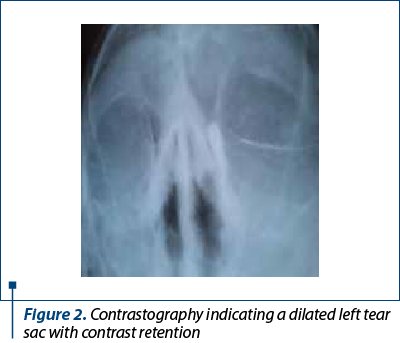

The therapeutic principles in nasolacrimal canal (NLC) stenosis are instrumental dilation, NLC stenting, endoscopic dacryocystorhinostomy (DCRS), external DCRS, and dacryocystectomy(5). The approaches are ophthalmic, ENT, and mixed. Before a therapeutic decision, it is essential to investigate using imaging by contrastography, which can objectify the obstruction of drainage through the nasolacrimal canal and the retention of the contrast substance in the tear sac(6) (Figure 2). Craniocerebral CT/orbit investigation provides additional data on nasal pathology and can be extremely useful before a radical surgical solution such as dacryocystectomy(7) (Figure 3).

Figure 2. Contrastography indicating a dilated left tear sac with contrast retention